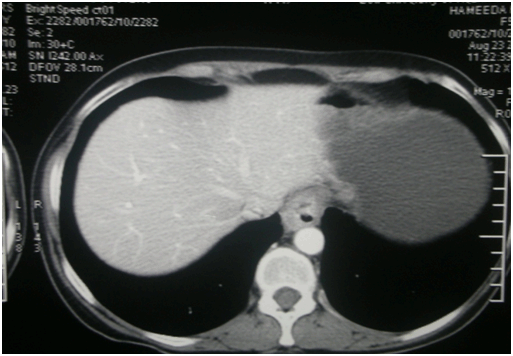

Patient 1: A 38-year-old female patient presented with progressive dysphagia for six months. CT-scan was done which showed T3N0 stage esophageal cancer (Figure 1). Diagnostic endoscopy revealed juxtra-carinal esophageal lesion which proved to be squamous cell carcinoma on biopsy (Figure 2). The patient was planned for a minimally invasive resection of the esophageal cancer with gastric tube construction. Abdominal part of the surgery was done videoscopically, thoracic part was done by open method due to dense juxtra-carinal adhesions. Eight lymph nodes were resected in the procedure and clear margins were obtained. The operative time was eleven hours, ICU stay of two days and hospital stay of nine days with no immediate post-operative complications. The patient did well in the initial post-operative period but eventually expired at a follow up of five months due to recurrent disease.

Figure 1: Computed tomography (CT) scan showing thickened esophageal margins.